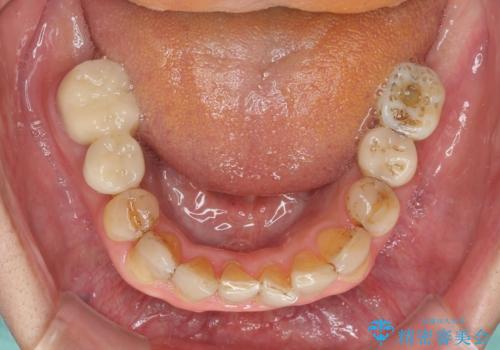

- 前歯のデコボコや、奥歯を咬んだときに痛みがあるとのことで来院された患者様です。

全体的に問題が多く、全てをしっかりと治療したいとのことでした。

全体的に中等度の歯周病と診断されたため、歯周外科処置やインプラントによる咬合回復から進めて行き、矯正治療による歯列改善を行った後にオールセラミッククラウンにて補綴することとしました。

矯正治療を希望して来院されましたが、歯周病を併発していたため、矯正治療開始前の処置が非常に多くなりました。特に歯槽骨の再生治療を行ったため、外科処置後の静置期間が長くなり、4年弱の治療期間となりました。